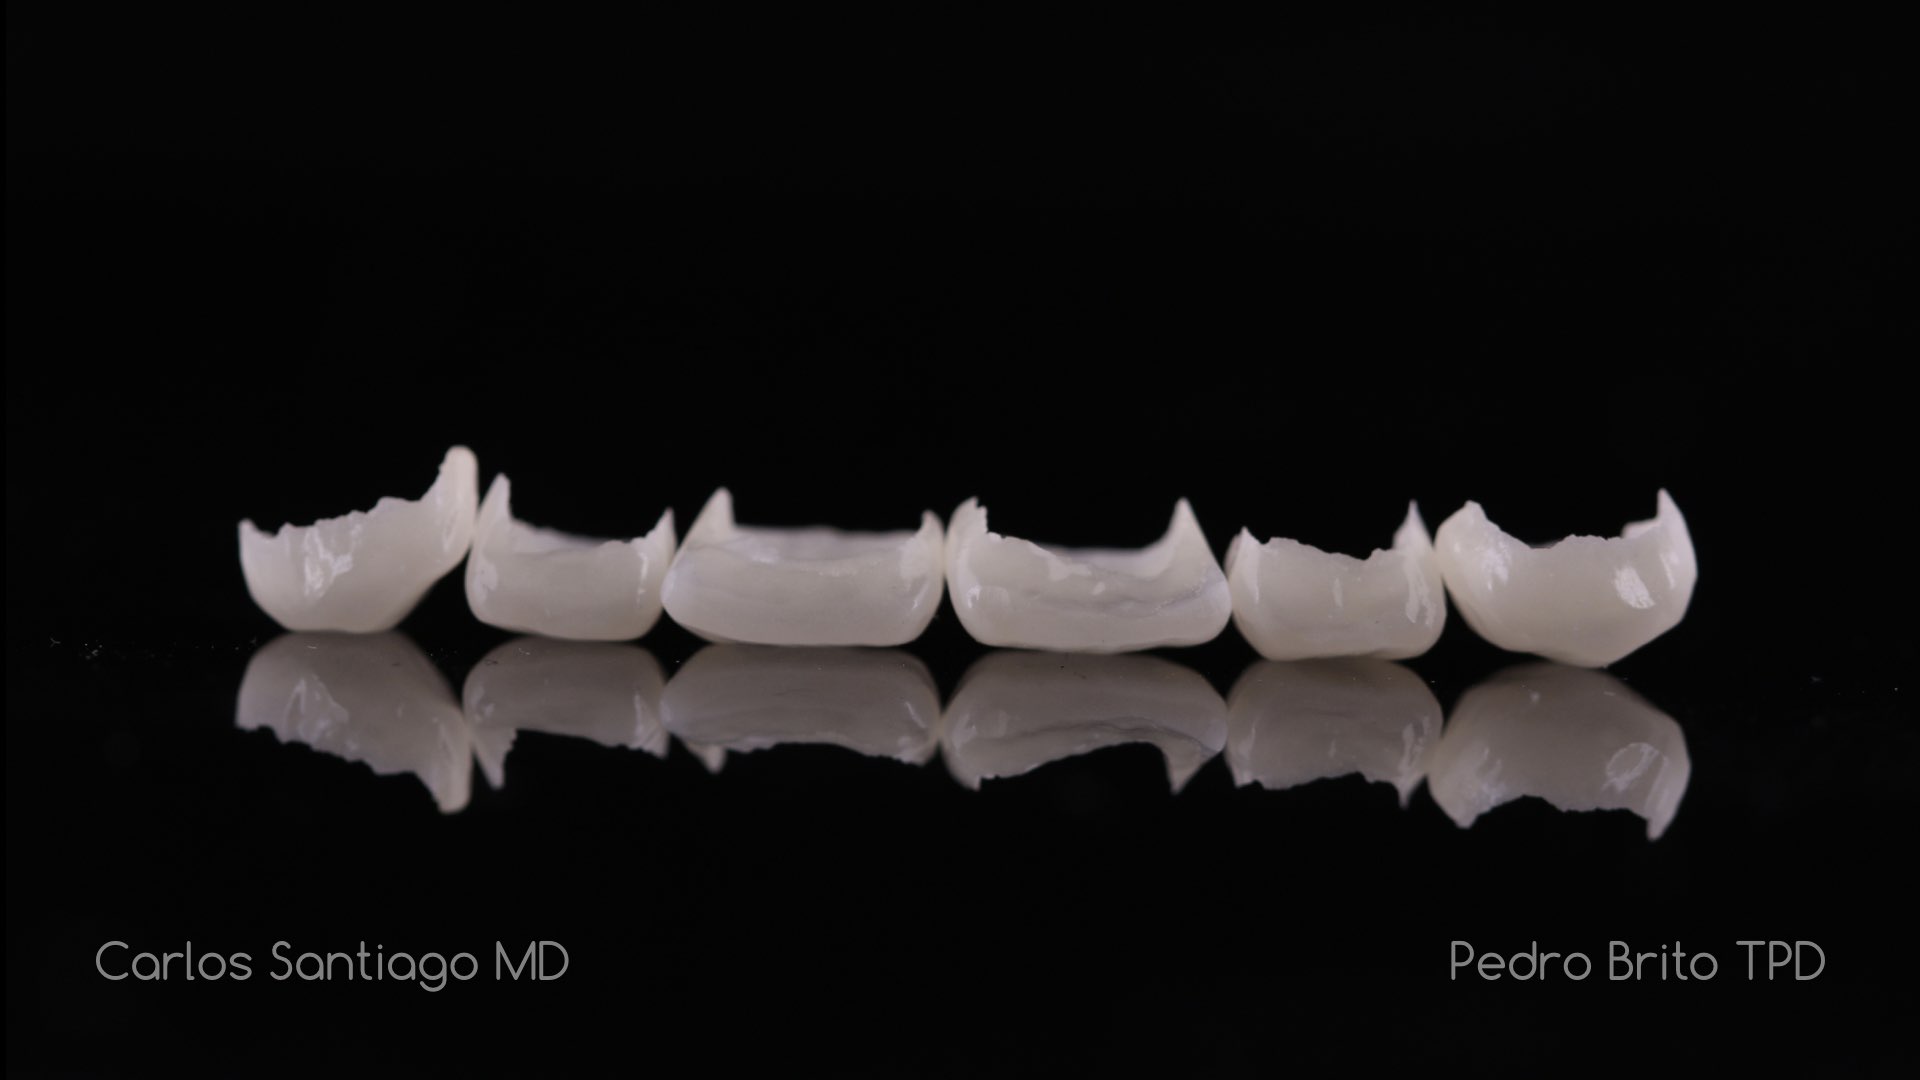

As Facetas Cerâmicas (lentes de contacto dentárias ou laminados), permitem corrigir da maneira mais estética e conservadora possível, problemas de forma e tamanho, côr e posição dos dentes, bem como substituir restaurações antigas e inestéticas.

São aderidas químicamente ao esmalte dentário de uma forma permanente, com o objectivo de melhorar a estética dos nossos pacientes.